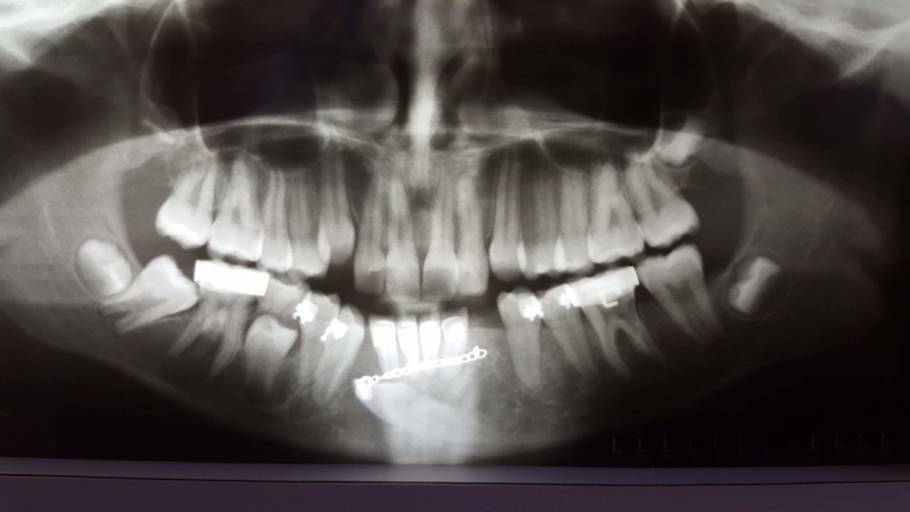

A la edad de 10 aproximadamente me extraen el premolar derecho por carie, a los 17/18 me extraen ambos premolares inferiores para desplazar la mordida hacia atrás. Y me ponen brackets, corrigiendo la postura de las piezas superiores y desplazando las inferiores hacia atrás. En 2019 cambio de dentista. Mi anterior especialista quería sacarme el premolar izquierdo para que la línea media desplazada hacia la izquierda se quede centrada. At the age of approximately 10, my right premolar was extracted due to decay, at 17/18 both lower premolars were extracted to move the bite backwards. And they put brackets on me, correcting the posture of the upper pieces and moving the lower ones back. In 2019 I change dentist. My previous specialist wanted to remove my left premolar so that the midline offset to the left would stay centered. My new specialist does not suggest this and ends the treatment in 2020, correcting the inclination of the teeth and giving it a better arch. Before the last visit prior to the removal of the appliances, the pandemic began and I found myself unable to go to the office, so I removed the appliances, arch and crowns myself with tools such as tweezers. From there I did not go to a visit with a dentist, I did not use containment. I want to correct the midline so that it is without a slope and centered with the middle of my face, as well as widen the palate with an expander for better comfort with my tongue and fix the issue of the spaces that were left in the lower part where my premolars were removed.